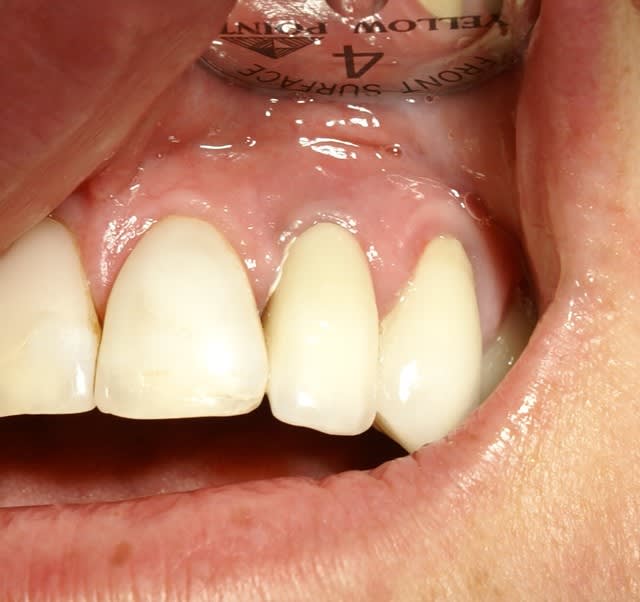

Ce cas est limite et aurait pu être traité en deux temps mais bon, j'ai opté pour y aller franco...

La seamine prochaine je vous montrerai la finition céramique.

22/03/2009 à 19h26

o.k. mais le trip reste le même que tu le fasses en une fois ou huit jours après. La bague de cica est déjà une mise en vitrine. D'autre part ce genre de truc ça gonfle tellement les premiers jours que ta patiente ne va pas sourire des masses ni même bouffer dans le secteur... Il faut relativiser d'autant plus qu'ici je me retrouvais short pour le calage primaire et tu noteras la classe II... La mise en place de la provisoire a eu lieu au retrait des sutures. Et il ne pourra pas s'agir d'une mise en charge, simplement d'une mise en vitrine.

Le didacticiel répondait à la question de Pluton qui se rendra vite compte que la mise en vitrine immédiate en zone prémaxillaire est un objectif peut-être souvent poursuivi mais plus rarement atteint. Mais peut-être qu'ailleurs l'herbe est plus verte ?